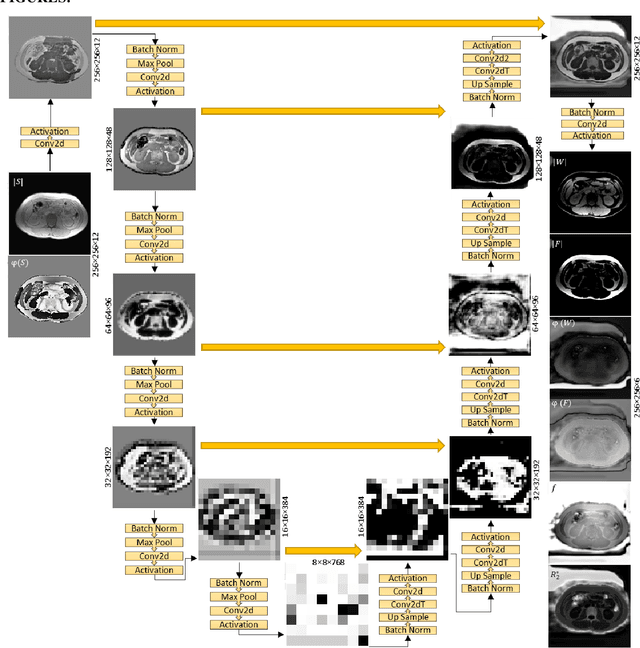

Abstract:Purpose: To use a deep neural network (DNN) for solving the optimization problem of water/fat separation and to compare supervised and unsupervised training. Methods: The current T2*-IDEAL algorithm for solving fat/water separation is dependent on initialization. Recently, deep neural networks (DNN) have been proposed to solve fat/water separation without the need for suitable initialization. However, this approach requires supervised training of DNN (STD) using the reference fat/water separation images. Here we propose two novel DNN water/fat separation methods 1) unsupervised training of DNN (UTD) using the physical forward problem as the cost function during training, and 2) no-training of DNN (NTD) using physical cost and backpropagation to directly reconstruct a single dataset. The STD, UTD and NTD methods were compared with the reference T2*-IDEAL. Results: All DNN methods generated consistent water/fat separation results that agreed well with T2*-IDEAL under proper initialization. Conclusion: The water/fat separation problem can be solved using unsupervised deep neural networks.